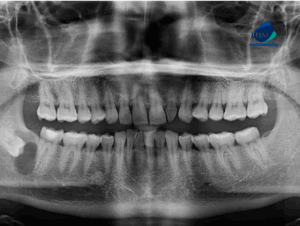

Paciente femenino de 39 años de edad, es referido al Instituto de Diagnóstico Maxilofacial – IDM para evaluación general.En la radiografía panorámica (Figura 1), se